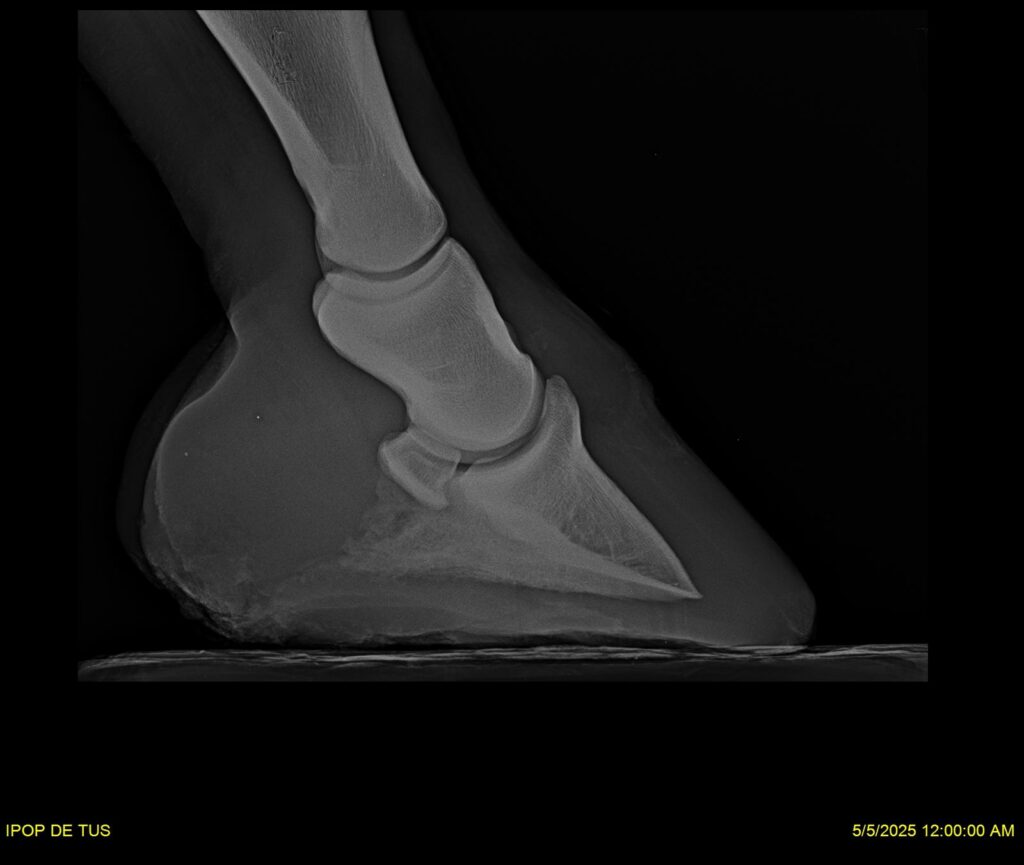

IPOP DE TUS, selle français, hongre, prendra 8 ans en 2026. LIFESTYLE x EROTICBLUS MONTOIS. Sans faute sur 125 et 130. Gentil cheval, respectueux avec des moyens et de la force. Transport OK, maréchalerie OK (pieds nus), santé RAS, Bilan clichés radios + clinique OK.

RADIOS ET CLINIQUE